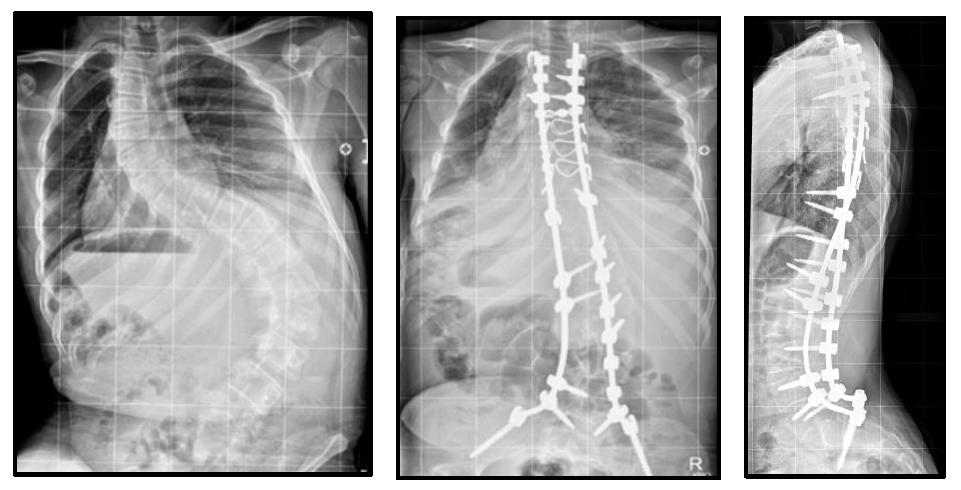

This surgery is for patients who have a moderate to large scoliosis or kyphosis that continues to worsen. It usually involves both the thoracic and lumbar spine.

While asleep facedown, an incision is made to expose the back muscles. Two titanium rods with special screws and hooks are attached carefully to the spine. Bone graft or synthetic bone is added to help fuse the spine bones together. Spinal cord monitoring is used to keep a check on the impulses from the brain to the limbs to ensure the spinal cord is functioning normally during surgery. A machine called a 'cell saver' is used to collect any blood lost, which is then filtered by the machine and given back to the patient.

The goal of this surgery for scoliosis or kyphosis is to fuse a section of the spine so that the deformity will not continue to worsen, and to gain some level of correction. It is not possible or desirable to fully straighten the spine. The titanium rods support the vertebrae while the bones are fusing together. The metal work is not removed and stays permanently attached to the spinal column. The titanium rods should not set off airport security alarms. There is usually no need for a brace after surgery.